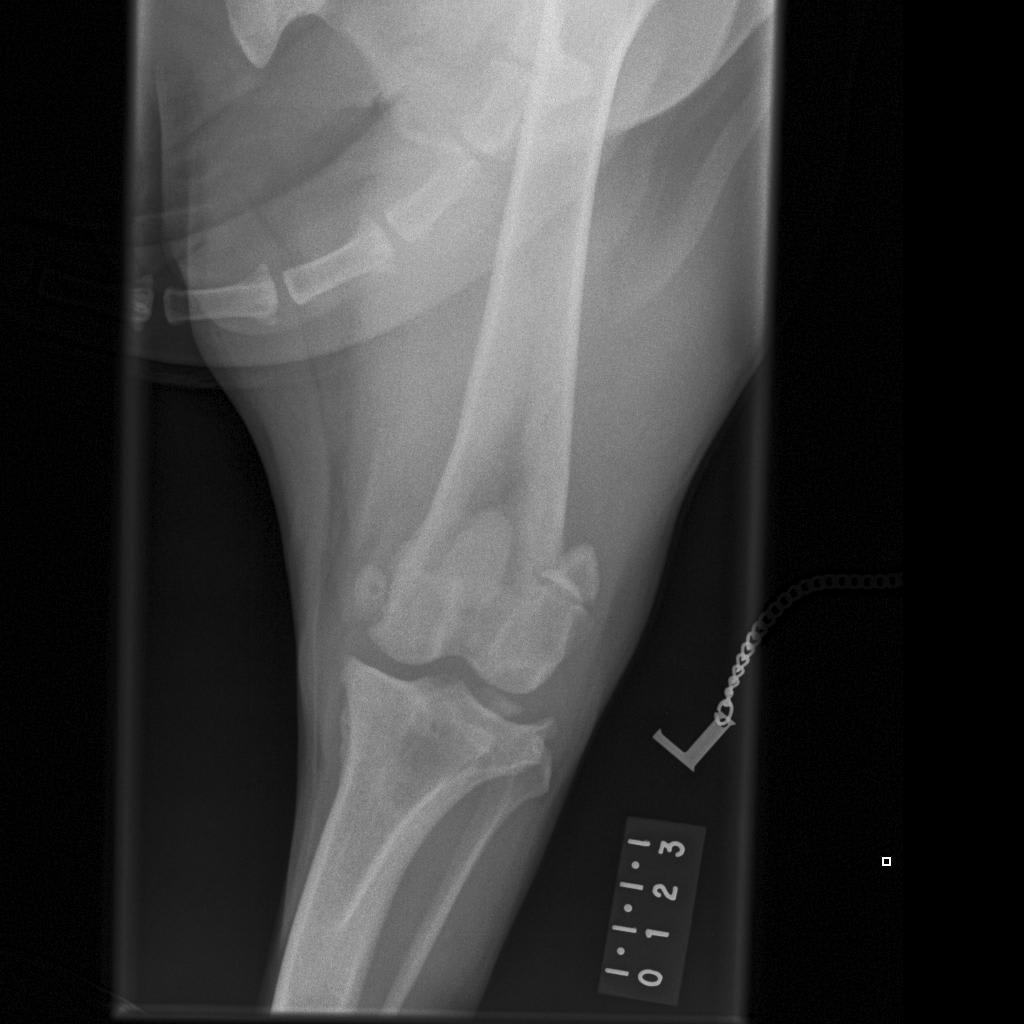

I’m after a 2nd opinion; not sure what to do.My dog is fully insured so not a decision based on cost.She damaged rear left cruciate ligament back in June. Since then her limp vanished only came back recently after intense running. My vet took x-rays (attached). She is a rescue dog,about 6 yrs old.I have also attached pic of her so you get an idea of the type of dog she is. 31kg. What’s best-operate or not? I want to do what’s best for her without undue pain or anxiety. I’m at a loss what to do.

The answer to your question really comes down to her examination and your goals. It is possible for a cruciate ligament to be partially torn or fully torn. If it is fully torn, the knee is unstable and surgery is the best option to stabilize the knee and slow down the development of arthritis in the joint. If the cruciate ligament is only partially torn, you can see signs like you have in Hambro where she seems pretty normal unless she injures the cruciate ligament again with high activity. For a large dog who is young, partial cruciate ligament injures are often problematic because they inhibit dogs from being able to play normally without being painful, but it sounds like Hambro has done well for 6 months. Another consideration is that if she has a partial tear, she may completely tear the cruciate ligament in the future which will necessitate surgery. There is also a potential complication of cruciate injuries that involve a tear in the meniscus. If that happens, she will be consistently lame and will need surgery. Unfortunately, only you can decide on the right answer for Hambro. Surgery provides the best possibility for return to normal activity without lameness, but certainly isn't without potential risks and complications. I have attached a handout on cruciate ligament injuries below. https://www.veterinarypartner.com/Content.plx?P=A&S=0&C=0&A=1975 Finally, if this is a partial cruciate injury and you would like to avoid surgery, I would recommend trying to find a rehabilitation veterinarian to help you with physical therapy exercises to strengthen Hambro. They will also be able to give you a second opinion. Hopefully you can find a vet in the UK at this site. http://www.caninerehabinstitute.com/Find_A_Therapist.html http://www.caninerehabinstitute.com/action.lasso Good luck! I hope that was helpful. Thanks for using PetCoach.